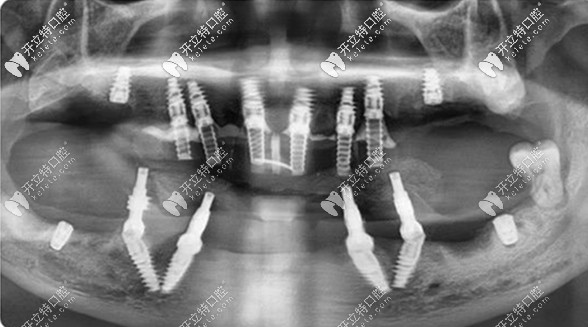

【終期方案為——all-on-4/6全口即拔即種 即刻負(fù)重的種植方案】

在充分了解了鄧?yán)蠋煹目谇磺闆r和訴求后,擅長全口缺牙修復(fù)的王鋒醫(yī)生為她定制了全口即拔即種的方案。

全口拔牙+即刻種牙+當(dāng)天用牙,對家在瀘州的鄧?yán)蠋焷碚f,不僅避免了來回奔波,還避免了缺牙期對自己形象、工作和日常生活的影響。